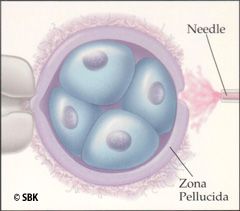

Paso 5: Maduración Asistida ("Assisted Hatching", AH): esta técnica, se utiliza para mejorar la probabilidad de la implantación del embrión. En la maduración asistida el embriólogo abre un pequeño agujero en la membrana externa del embrión conocida como zona pelúcida. Esta abertura mejora la habilidad del embrión de dejar su "caparazón" e implantarse en el revestimiento uterino. Entre los pacientes que pueden beneficiar de la maduración asistida, se incluye aquellos con intentos de fertilización in vitro fracasados, baja tasa de crecimiento del embrión, fragmentación citoplasmática moderada a excesiva y mujeres con edad materna avanzada.

Paso 5: Maduración Asistida ("Assisted Hatching", AH): esta técnica, se utiliza para mejorar la probabilidad de la implantación del embrión. En la maduración asistida el embriólogo abre un pequeño agujero en la membrana externa del embrión conocida como zona pelúcida. Esta abertura mejora la habilidad del embrión de dejar su "caparazón" e implantarse en el revestimiento uterino. Entre los pacientes que pueden beneficiar de la maduración asistida, se incluye aquellos con intentos de fertilización in vitro fracasados, baja tasa de crecimiento del embrión, fragmentación citoplasmática moderada a excesiva y mujeres con edad materna avanzada.

Maduración Asistida ("Assisted Hatching", AH)

Esta técnica es utilizada para mejorar la implantación del embrión. En la maduración asistida el embriólogo abre un pequeño agujero en la membrana externa del embrión conocida como zona pelúcida. Esta abertura mejora la habilidad del embrión de dejar su "caparazón" e implantarse en el revestimiento uterino.